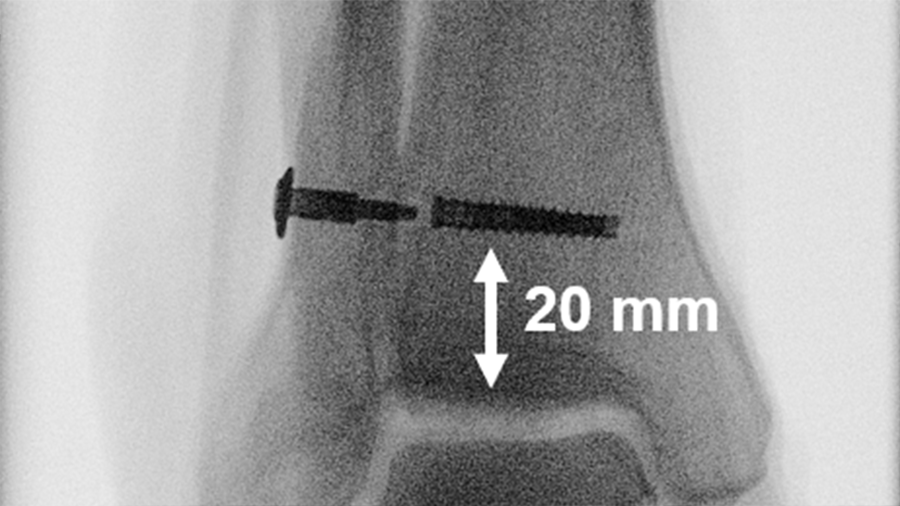

Sixteen pairs of human anatomical specimen, namly knees, were used to simulate either two-part transverse simple AO/OTA 34C1 or five-part complex AO/OTA 34C3 patella fractures by means of osteotomies, with each fracture model being created in six pairs. The complex fracture pattern was characterized by a medial and a lateral proximal fragment, together with an inferomedial, an inferolateral and an inferior fragment mimicking comminution around the distal patellar pole. The specimens with simple fractures were pairwise assigned for fixation with either tension band wiring through two parallel cannulated screws, or a lateral rim variable angle locking plate. The knees with complex fractures were pairwise treated with either tension band wiring through two parallel cannulated screws plus circumferential cerclage wiring, or a lateral rim variable angle locking plate (Fig 2).

Each specimen was tested over 5000 cycles by pulling on the quadriceps tendon, simulating active knee extension and passive knee flexion within the range from 90° flexion to full knee extension. Interfragmentary movements were captured by means of motion tracking.